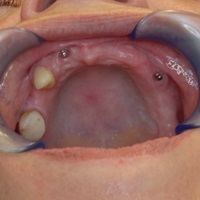

Pacjentka głosiła sie do naszego gabinetu do leczenia z osadzonym mikroimplantem w pozycji lewej dolnej dwójki. Siostrzany implant w pozycji prawej dolnej dwójki wypadł wcześniej, około 1,5 roku od implantacji. Odtworzono przedsionek i dziąsło rogowaciejące, osadzono dwa implanty, jednoczasowo z regeneracją kości. Dopiero na etapie ostatecznej rekonstrukcji protetycznej usunięto zachowany mikroimplant. To się nazywa motywacja do leczenia! Pacjentka przygotowywała sie na ślub prawnuczki :)